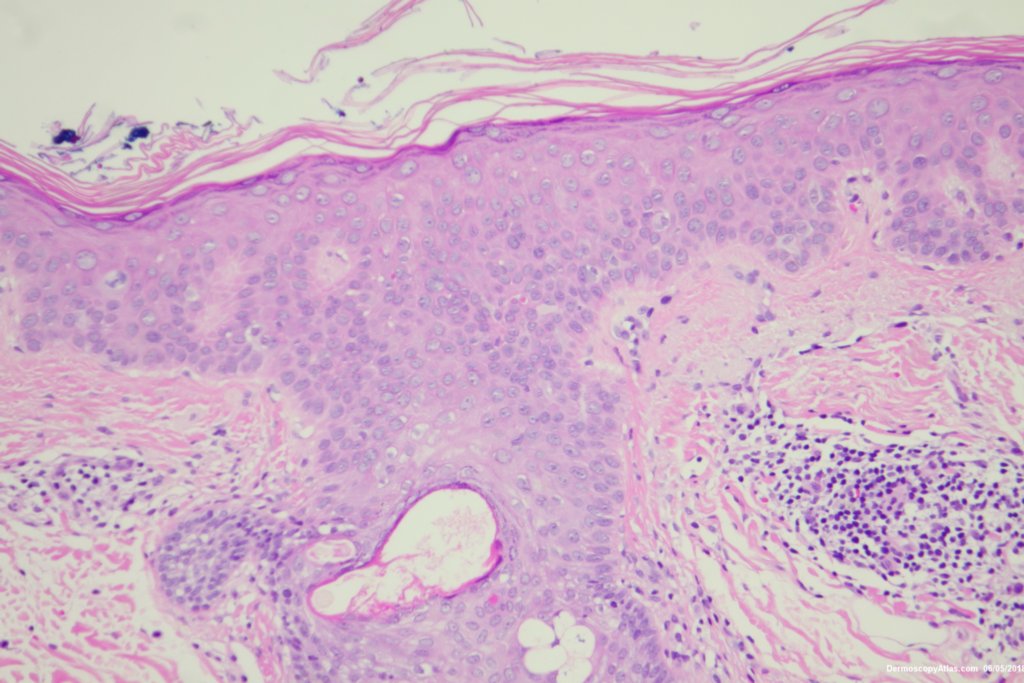

Image Number #3444 (Pigmented Intraepidermal carcinoma)

Diagnosis: Pigmented Intraepidermal carcinoma

Some pigmented lesions look melanocytic, However this is a pigmented intraepidermal carcinoma. Some areas show more full thickness atypia than others. The dermatoscopy shows some dots in rows but there are other grey dots showing regression at one edge.